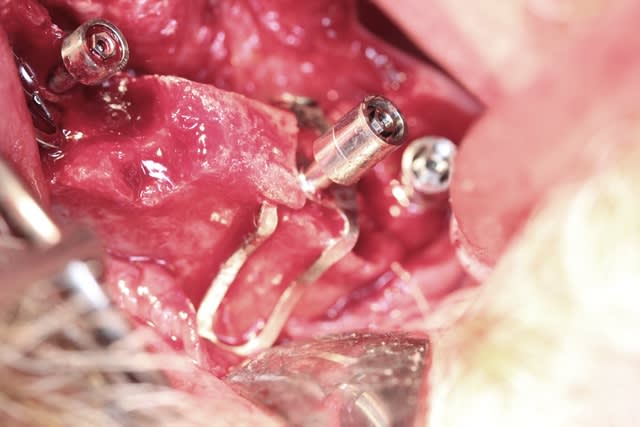

Voilà c est fait depuis hier mardi...

Me suis bien fait chier avec les canines : il y a avait plus rien...

Bref 2 ptérygo, 2 plaques en molaires, deux disk en canine 1 simple et un double, un cylindre ds le trou naso palatin, 2 triple disk en 11 12 et 21 22 et enfin un monodisk en 24...ça a été galère mais c est fait

01/10/2013 à 06h47

Opéré mardi matin

Posé samedi matin

Photos un peu flou car implanto chaude et j ai pris juste l appareil deux fois pour tirer le portrait des deux plaques

En plus j ai mal sélectionné le mode : je devais les faire en manuel ouverture 16 vitesse 1/200 mais j ai selcetionné priorité à l ouverture et la vitesse était trop lente d où flou :-((((((((((